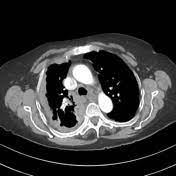

Early Mesothelioma Ct - Mesothelioma Imaging Scans Using X Rays To Detect Cancer - These are the ajcc early stages of malignant mesothelioma cancer:. Business details location of this business 265 church st fl 11 1. mesothelioma, a rare form of cancer that develops in the protective lining of many internal organs, is caused by exposure to asbestos, such as inhaling or ingesting asbestos in the workplace. Malignant pleural mesothelioma (mpm) is a neoplasm of mesodermal origin and is associated with exposure to asbestos.mpm has a poor prognosis, but detection in early stages can significantly increase patient survival, as distant metastasis occurs at considerably later stages. mesothelioma can accurately be described as a deadly and aggressive form of cancer. Therefore, developments in technology that allow for early detection are crucial for patient survival.

These are the ajcc early stages of malignant mesothelioma cancer: Survival is higher in people whose disease is recognized early. Aside from angiographic examinations, thoracic ct scans are routinely performed with a variety of protocols, with many institutions using early phases for scanning the chest and delayed phases for the abdomen. Over ct lung screening of smokers, canadian researchers are developing a unique ct screening program designed to focus on patients who have been exposed to asbestos as a tool for early detection of malignant mesothelioma. Pleural mesothelioma asbestos exposure pleural plaque. Devotes nearly 100 percent of its resources to mesothelioma cases and has been doing so for over 30 years. mesothelioma is typically a preventable disease that is caused through inhaling or ingesting microscopic asbestos fibers. Symptoms of mesothelioma may not appear for 20 to 50 years after the exposure. In heavy smokers, early detection of lung cancer with chest ct scan leads to a 20% mortality reduction. One of the newest developments in technology is a breath test. Your doctor may also refer to the cancer stage of mesothelioma as early or advanced. mesothelioma is a malignant tumor of the pleura that is mainly caused by chronic exposure to asbestos fibers and more than 40 years of exposure are needed to develop the disease. Large‐scale screening of construction workers for early diagnosis of asbestos‐related mesothelioma by n‐erc elisa.

A problem swallowing, which is known as dysphagia, is not always associated with … continued The case of a mesothelioma patient in spain could suggest that having a hard time swallowing could be a rare, early sign of mesothelioma. Magnetic resonance imaging (mri) scan. Ability to examine the time course of mark ers and their prognostic ability to detect mm prior to detection via chest ct scan. With standard treatment, average mesothelioma survival is about a year. Imaging is usually performed once symptoms become evident and prior to performing an invasive biopsy, yendamuri said. However, mesothelioma is often diagnosed once it has advanced, as often the early symptoms can go unnoticed. early info about mesothelioma, asbestosis, lung cancer and how to treatment, therapy, and prognosis, diagnosis, mesothelioma chemotherapy. Business details location of this business 265 church st fl 11 1. A ct scan by itself, however, cannot provide unequivocal mesothelioma diagnosis, although a ct guided biopsy—which uses a ct scan to guide the biopsy needle into the tumor—can. At the international centre for thoracic surgery (icts), we have put together a health screening plan to screen for early lung cancer. Breath test developed for early mesothelioma detection august 6, 2019. Additionally, it is not known if early discovery of the disease affects prognosis 7 .

Malignant pleural mesothelioma (mpm) is a neoplasm of mesodermal origin and is associated with exposure to asbestos.mpm has a poor prognosis, but detection in early stages can significantly increase patient survival, as distant metastasis occurs at considerably later stages. Increasingly, fdg pet/ct is used for diagnosis and management of malignant pleural mesothelioma. An mri scan creates detailed images of the body's soft tissues using radio waves and magnets. While the exact cause of mesothelioma is unknown, the primary risk factor is exposure to asbestos fibers. The mesothelioma is in the pleural lining of the chest wall on only one side of the chest. Asbestosis is often detected through ct scans. Understanding the symptoms mesothelioma is a progressive disease in that it continues to worsen without intervention. Devotes nearly 100 percent of its resources to mesothelioma cases and has been doing so for over 30 years.

A ct scan by itself, however, cannot provide unequivocal mesothelioma diagnosis, although a ct guided biopsy—which uses a ct scan to guide the biopsy needle into the tumor—can. This stage describes patients whose tumors haven't started growing and spreading beyond their origin. Magnetic resonance imaging (mri) scan. Positron emission tomography (pet) scan. It may not be affecting the pleura lining in the diaphragm, the mediastinum, or the pleura that covers the lung. early detection of mesothelioma or any other cancer is the crucial factor for increasing life expectancy. Your source for mesothelioma, news, including treatments for malignant pleural mesothelioma, clinical trials for peritoneal mesothelioma, asbestos related lung cancer, asbestosis (asbestoses), and asbestos information. early info about mesothelioma, asbestosis, lung cancer and how to treatment, therapy, and prognosis, diagnosis, mesothelioma chemotherapy. The fibers become lodged in the lining of the lungs, abdomen or heart and can lay dormant for decades before symptoms start to show. About early, lucarelli, sweeney & It is the least advanced stage. Each stage details how far the tumor has spread from where it first appeared in the pleura, the protective lining of the lungs. Is a national law firm recognized for its representation of over 1800 hardworking men and women who have been exposed to asbestos and diagnosed with mesothelioma.